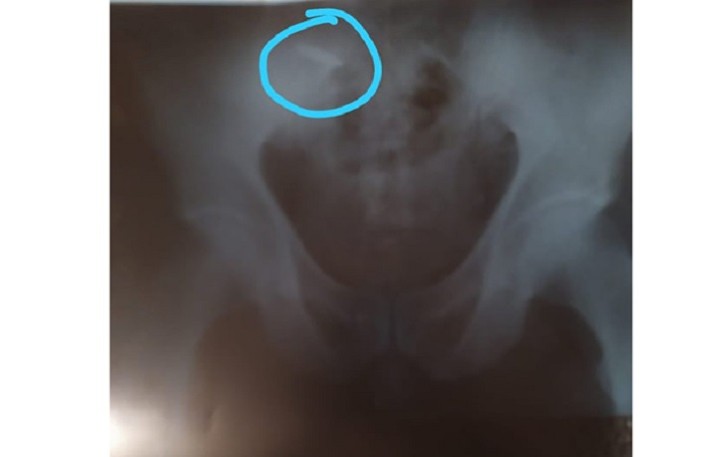

Bu barədə “Qafqazinfo”ya onun oğlu Şükür Əhmədli məlumat verib. O qeyd edib ki, atası 1992-1993 -cü ildə Qarabağ döyüşlərində iştirak edərək Füzuli rayonu Qacar kəndində sol ayaq nahiyəsindən güllə yarası alıb: “Artıq 29 ildir ki, güllə atamın bədənindədir. Güllə daxil olan hissə, yəni sol hissədən sümüyü çürüməyə başlayıb. Bu da bədəndə çox pis ağrılara səbəb olur. Bununla yanaşı, ağır ürək xəstəliyi, şəkərli diabet və yüksək təzyiqdən əziyyət çəkir. Son aylarda ağrıları daha da şiddətlənib. Maddi imkan da müalicə üçün şərait yaratmır. Evi dolandıran təkcə mənəm.

Atam mütəmadi olaraq dərmanlardan istifadə edir. Qardaşım da tələbədir. Tibbi ekspertizanın rəyinə əsasən, atamın qrup əlilliyi ləğv edilib. Heç bir müayinə etmədən, sadəcə şifahi olaraq deyilib ki, heç bir şeyi yoxdur, ona görə də əlillik düşmür. Vətən, qeyrət uğrunda canından keçən insanların halına bu qədər də laqeyd yanaşmaq olmaz”.